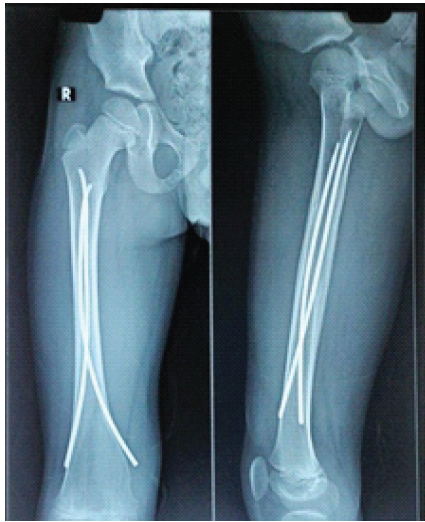

Post-operatively, patients were followed for 6 months with evaluations at 6, 12, and 24 weeks. Partial weight bearing was started at 6 weeks and gradually increased to full weight bearing once radiographic evidence of fracture union was observed on anteroposterior and lateral X-rays. During follow-up, patients were assessed for the time to fracture union, the occurrence of complications, such as superficial or deep infections, implant prominence or migration, fracture angulation, loss of reduction, fracture collapse, limb shortening, and range of motion. In addition, at the past follow-up, an orthoroentgenogram (scanogram) was performed to check whether there was limb length discrepancy (LLD). Pain, malalignment, LLD, and complications were reported and classified according to Flynn’s criteria. Ethical clearance was taken from the institute. In the image, Fig. 1 is showing mid 1/3rd shaft of femur fracture. Fig. 2 & 3 is showing immediate post-operative X-ray. Fig. 4 shows 2 years of follow-up, and Fig. 5 shows the X-ray after hardware extraction.

Figure 4: After 2 years of follow-up.